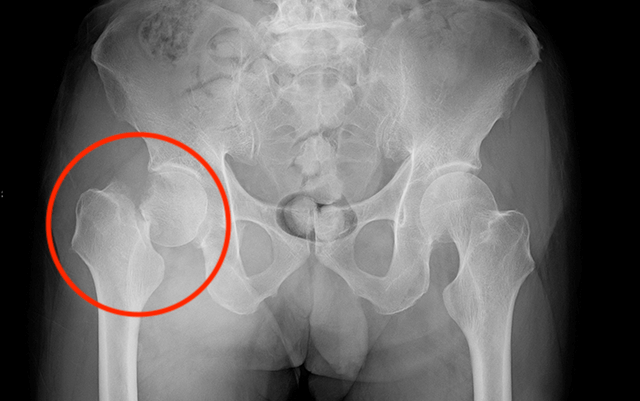

「左大腿骨骨折」と診断されました。

松岡正海騎手「左大腿骨骨折」で全治6ヶ月?!

大腿骨とは四肢動物の後肢において近位部を構成する長骨。

分かりやすく言うと、足の付根の部分を指します。

診断の結果は全治6ヶ月。

【追記】松岡正海騎手 手術が無事成功!

2020年2月20日に松岡正海騎手の状態が公式発表されました。

左大腿骨骨折で戦列を離れている松岡正海騎手(35)=美・フリー=は、先週の12日に茨城県内の病院で骨折部をボルトで固定する手術を無事終了。「歩けるまでに3カ月はかかると言われていますが、早期復帰を目指して頑張ります」とカムバックに意気込み。

歩けるには3ヶ月かかるとのこと。